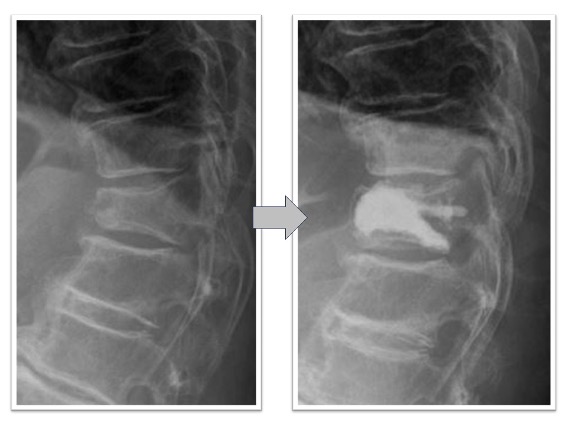

経皮的椎体形成術実例(*患者様の許可を得て掲載しています)

胸椎圧迫骨折

胸椎圧迫骨折後、遷延する腰痛と骨癒合不良を認めていた椎体に対してBKPを実施しています。治療後レントゲン画像では椎体内に注入された骨セメントと椎体高が改善していることが確認できます。腰痛改善し術翌日に退院となっています。